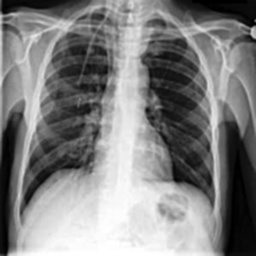

These steps collectively enhance the critical features of the CXR images, aiding in more accurate analysis. Figure2 shows the comparison between CXR images before and after preprocessing highlighting the enhanced clarity and feature extraction achieved through the applied filters.

(a) Before Preprocessing

(b) After Preprocessing

Figure 2: Comparison of CXR Images Before and After Preprocessing